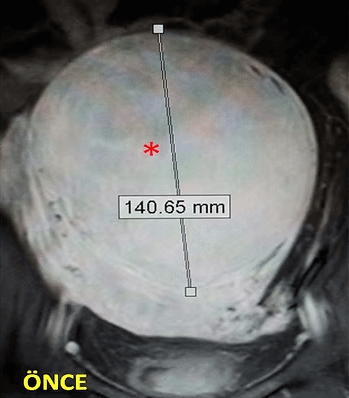

41 yaşında, kabızlık, gaz ve sık idrara çıkma şikayetleri var. Emar’da karını dolduran dev miyom (*) mevcut. Miyomektomi önerilmiş, ancak operasyonda rahimin alınabileceği söylenmiş. Embolizasyondan sonra dev miyomun ve bir başka küçük miyomun öldüğü ve küçüldüğü izleniyor. 7 ay sonra hasta şikayeti kalmamıştır.